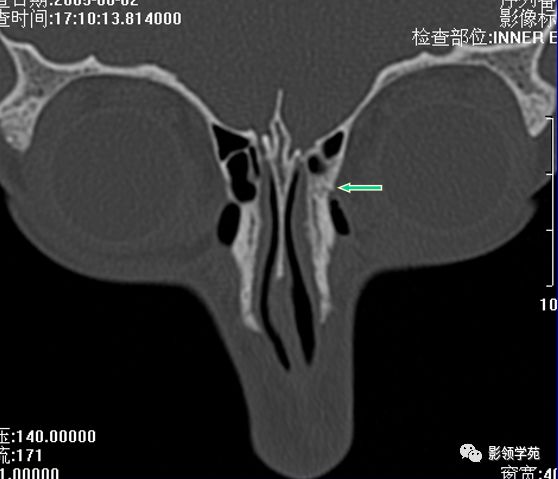

右侧鼻骨线形骨折

鼻骨线形骨折

左侧鼻骨线形骨折